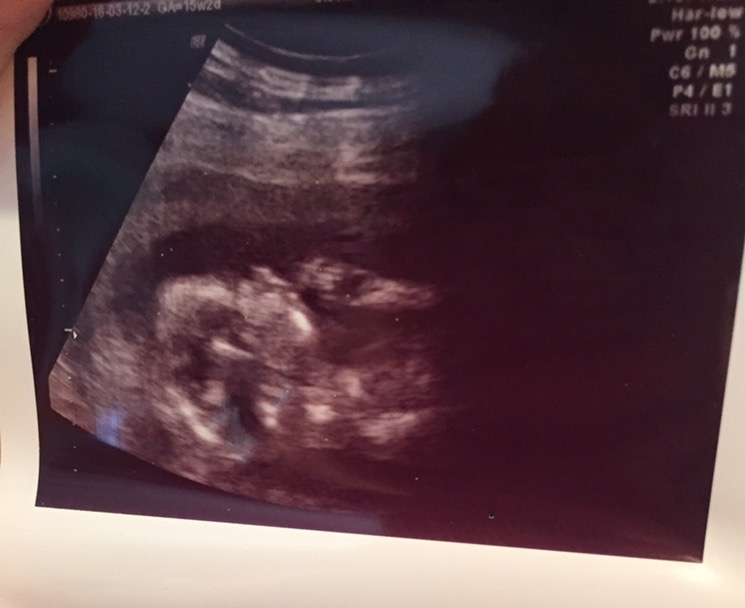

15 week elective sono to find out the sex (it's a boy!!) he wouldn't hold still for any clear pics, but I liked this one as he looks like he is posing for an 80s glamour shot with his fist at his chin